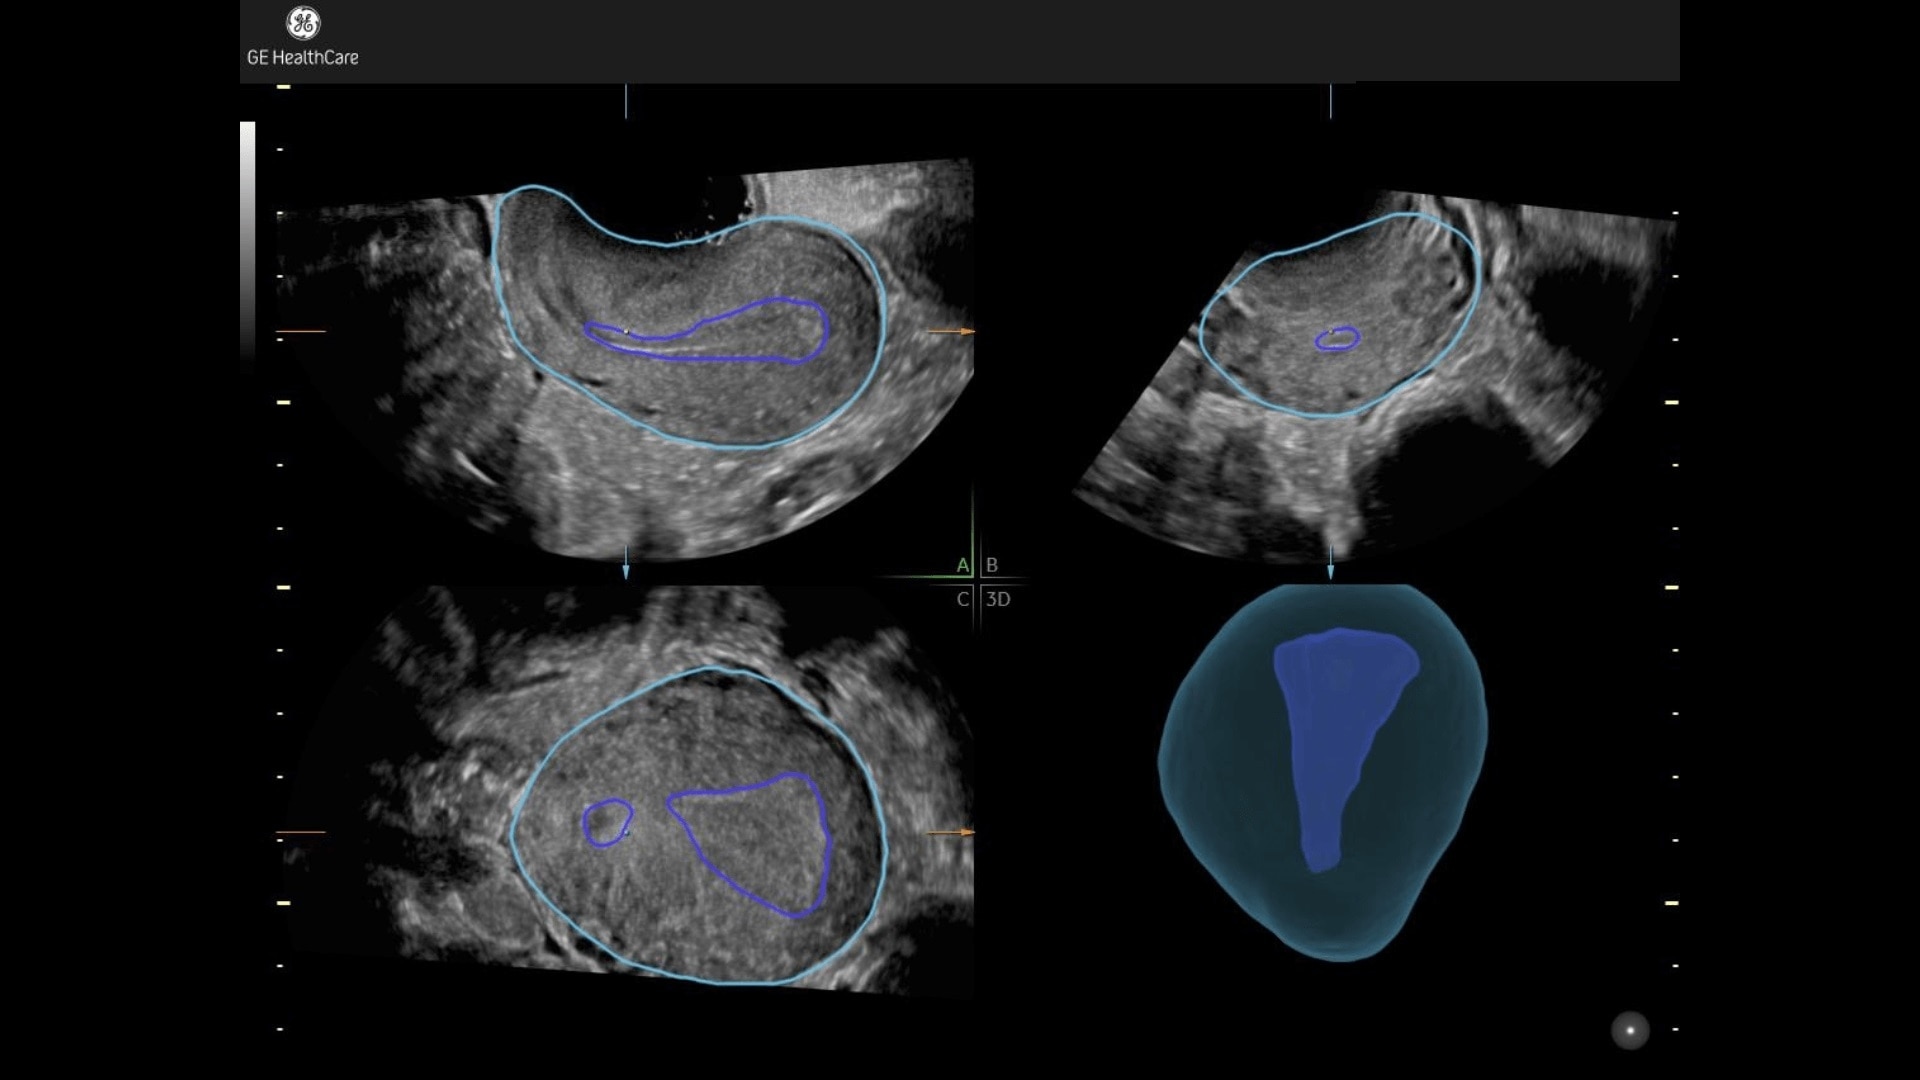

Fibroid Mapping

Uterine fibroid location & size highlighted in 3D.

Uterine fibroid location & size highlighted in 3D

• Illustrates position of fibroid in relation to uterus in 3D.

• Classify each fibroid according to FIGO© classification.

• Simplify communication with colleagues, referring pysicians and patient.